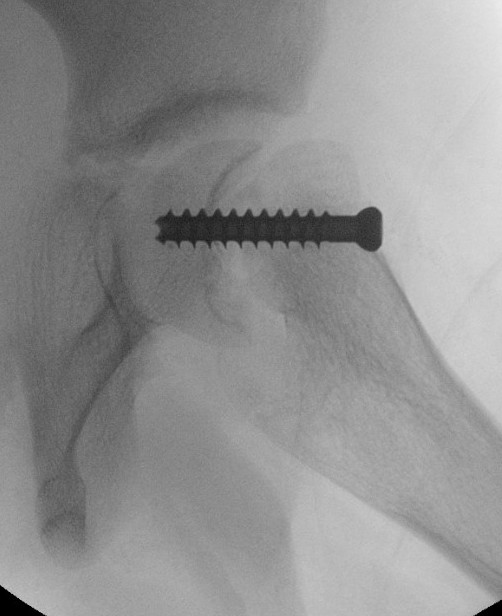

Base of neck / Kramer

Technique

- closing wedge anterior and superior

Disadvantage

- risk AVN

- shortens neck further - worsens LLD